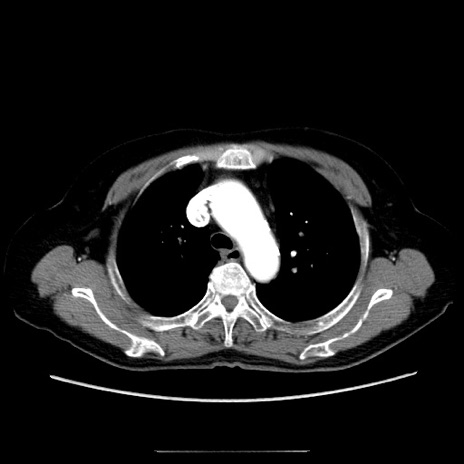

症例5(横断像)

【症例】70歳代女性

【主訴】お腹が張る

【現病歴】1週間くらい前から腹部膨満の自覚あり。昨日夜から増悪したため、本日救急外来受診。

【身体所見】意識清明、BT 36.5℃、BP 165/106mmHg、HR 80bpm、SpO2 98%、腹部:膨満、軟、自発痛・圧痛なし、触診にて不快感あり、腸蠕動音:減弱

【データ】WBC 12600、CRP 1.04